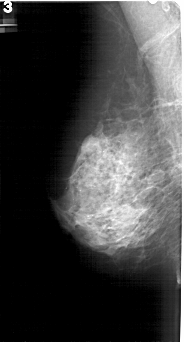

A_1196_1.LEFT_MLO

LEFT_MLO LINES 5116 PIXELS_PER_LINE 2746 BITS_PER_PIXEL 12 RESOLUTION 43.5 NON_OVERLAY